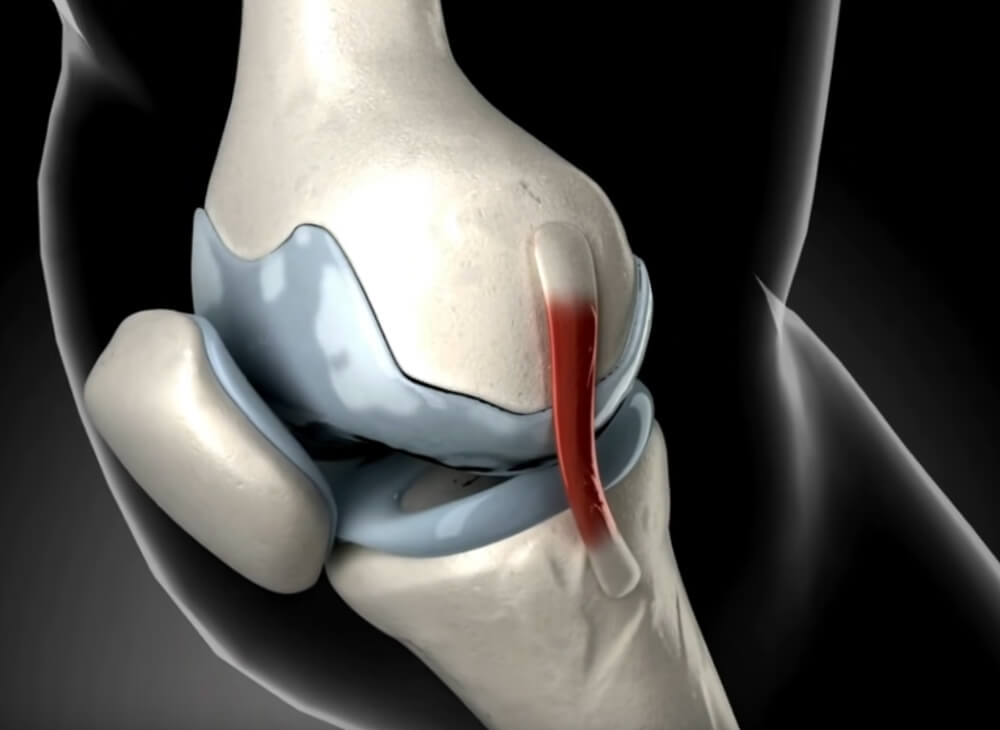

Zwischen allen Gelenken befinden sich Knorpel, welche die Gelenke schützen.

Diese Knorpel werden über die Gelenkflüssigkeit mit Nährstoffen versorgt.

Wenn die Knorpel zu wenig Gelenkflüssigkeit erhalten, trocknen sie aus und werden brüchig.

Dies führt dazu, dass sich die Knorpelpuffer zwischen den Gelenken abbauen.

Die Knorpel können die Gelenke daraufhin nicht mehr ausreichend schützen und die Gelenkknochen reiben aufeinander.

Die Folge: Die Gelenke entzünden sich.

Das kann wiederum zu starken Schmerzen führen.